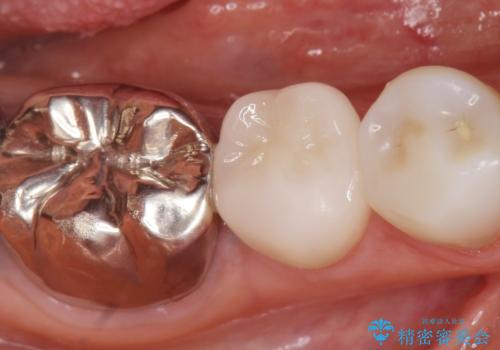

銀歯の下が虫歯になっている セラミックインレー 30代女性